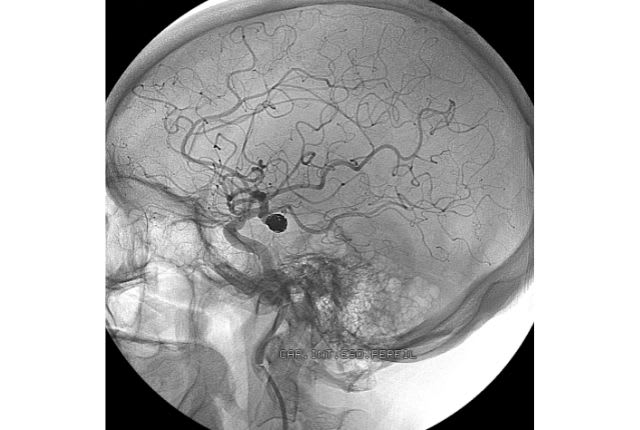

La rupture d’anévrisme au cerveau

L’anévrisme cérébral correspond à une fissure ou à une rupture d’une artère qui irrigue le cerveau, avec pour conséquence une hémorragie intracrânienne et un accident vasculaire cérébral (AVC). C’est la forme d’anévrisme la plus courante selon la Haute Autorité de Santé, affectant majoritairement les femmes (60 à 65 %), particulièrement sur la tranche d’âge de 50 à 60 ans, en raison de facteurs hormonaux.

Pour diagnostiquer une rupture d’anévrisme, le spécialiste effectue des examens propres au type d’anévrisme suspecté : un scanner ou une IRM pour confirmer l’existence d’une hémorragie, une artériographie (ou angiographie) pour évaluer l’état des artères et situer précisément l’hémorragie, ou encore une ponction lombaire.